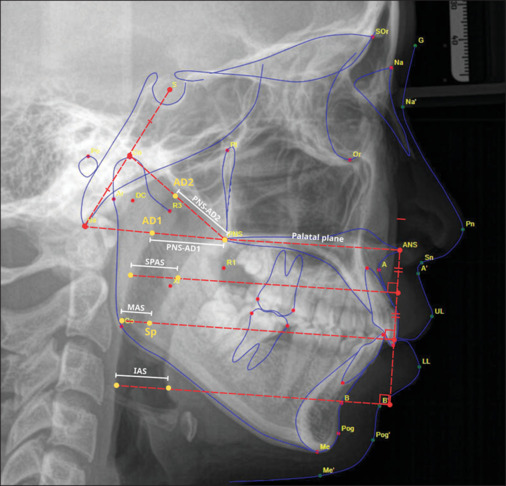

Objective: To assess the correlation between pharyngeal airway dimension measurements via cephalometrics and those via cone beam computed tomography (CBCT) in patients with skeletal Class II malocclusions.

Subjects and methods: In this cross-sectional retrospective study, we reviewed the medical records of 106 patients referred for both CBCT and cephalometric imaging between 2022 and 2023 at Can Tho University of Medicine and Pharmacy Hospital. Pharyngeal airway dimensions were measured using WEBCEPH software for cephalometric analysis and Mimics Research software for CBCT image processing and analysis.

Results: A strong correlation between cephalometric films and CBCT images was observed regarding airway parameters. The airway volume exhibited a negative correlation with the ANB and SN-GoGn angles and a positive correlation with the SNB angle.

Conclusions: Cephalometric analysis may serve as a fundamental screening tool to provide valuable information regarding the morphological characteristics of the airway as an alternative to CBCT.